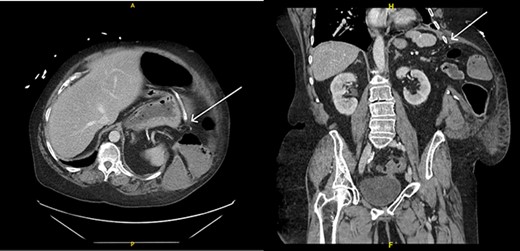

Upon evaluation, the patient was found to have white blood cells 20.1 (4–10.9), with unremarkable vitals and no signs of peritonitis on examination. Computerized tomography (CT) abdomen/pelvis revealed a large bowel obstruction with pneumatosis intestinalis of the right colon secondary to a sigmoid mass (Fig. 1). Upon surgical review of the images, the patient’s CT also showed a left-sided intercostal hernia containing loops of large bowel that was not initially reported by the radiologist (Fig. 2). The mechanism of this was unclear; however, it has been hypothesized that it could be a result of a combination of severe cough related to patient’s recent pneumonia and underlying COPD, or trauma to the left chest wall allegedly sustained at the previous facility.

Pneumatosis intestinalis of the right colon (thin arrow) and sigmoid mass (thick arrow).

Left intercostal hernia containing loops of large bowel, axial view (left), coronal view (right).